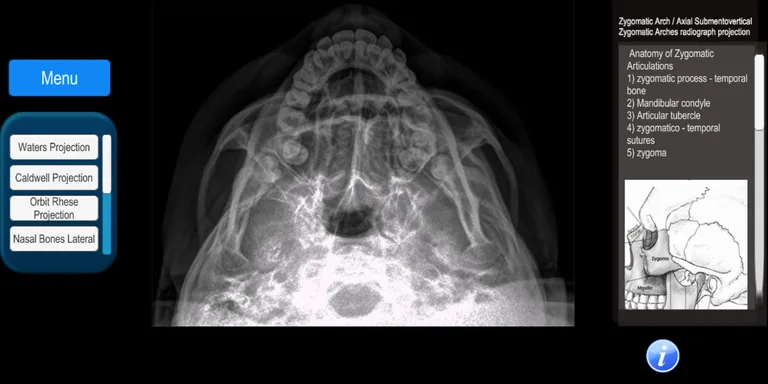

It is an app that allows the user to know the radiological projections that are used daily in a patient care. It covers all areas of the human body with more than 100 digital radiographs: skull, maxillofacial, spine, chest, abdomen, pelvis, upper and lower extremities.

The anatomy of the studied area is described, as well as the technique used for positioning the radiographic projection.